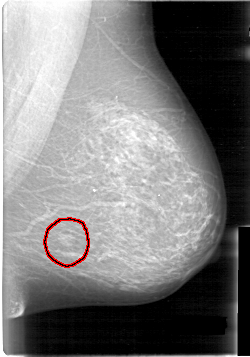

D_4014_1.LEFT_MLO

LEFT_MLO LINES 5341 PIXELS_PER_LINE 3736 BITS_PER_PIXEL 12 RESOLUTION 43.5 OVERLAY

FILE: D_4014_1.LEFT_MLO.OVERLAY

TOTAL_ABNORMALITIES 1

ABNORMALITY 1

LESION_TYPE MASS SHAPE LOBULATED MARGINS OBSCURED

ASSESSMENT 0

SUBTLETY 5

PATHOLOGY BENIGN

TOTAL_OUTLINES 1

BOUNDARY